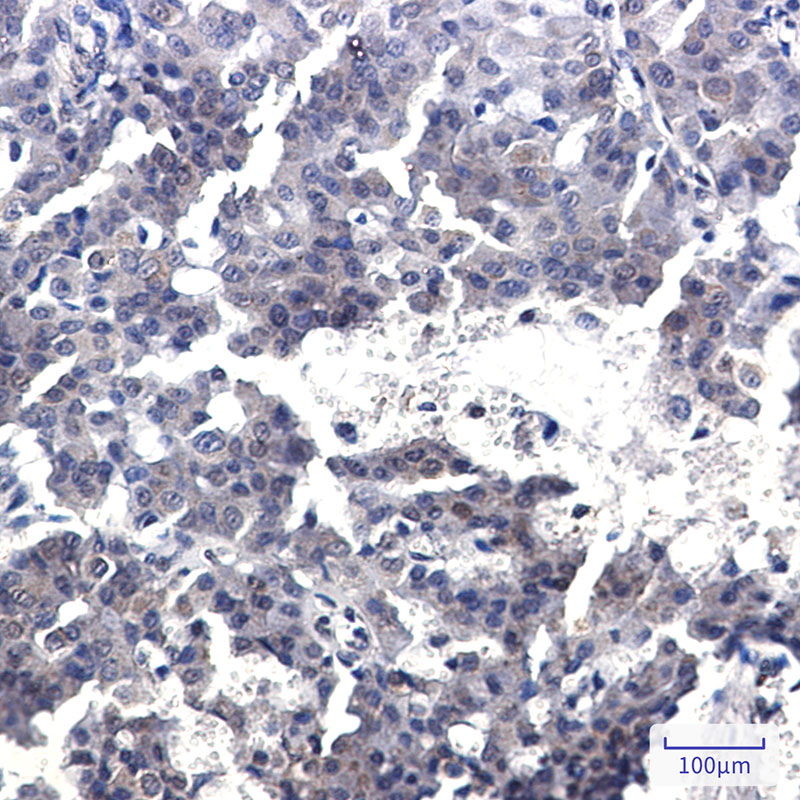

Product Image

| IHC | 1/50-1/100 |